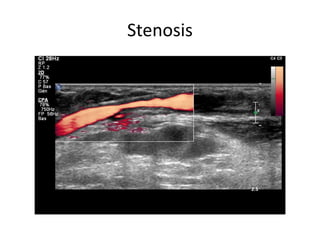

Color Doppler ultrasound

Stenosis